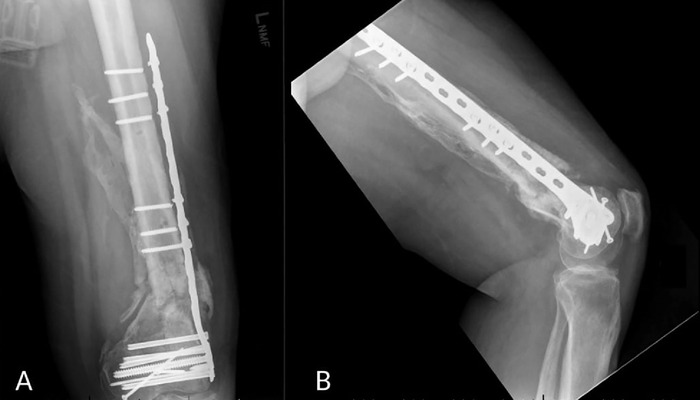

Case report: A 54-year-old male was involved in a high-speed motor vehicle accident that resulted in a left distal femur fracture. The patient underwent multiple reconstructive procedures that were complicated by hardware failure and recurrent nonunion. Prior to the sixth reconstruction, a superficial femoral artery occlusion was discovered and addressed with endarterectomy. The sixth and final procedure resulted in osseous union and stable fixation of the femur fracture.

Conclusion: A missed superficial femoral artery occlusion likely contributed to the delay in achieving osseous union of a traumatic comminuted distal femur fracture.